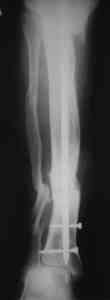

Пример (пациент 46 лет, лечился у нас 4 года назад, внутренний остеосинтез выполнен с определенными погрешностями, но перелом сросся и рецидива инфекции не было): рис. 1,2 - при переводе к нам в институт, рис. 3 - после микрохирругической пластики, рис. 4, 5 - после интрамедуллярного остеосинтеза, рис. 6, 7, 8 - внешний вид и рентгенограммы после окончания лечения